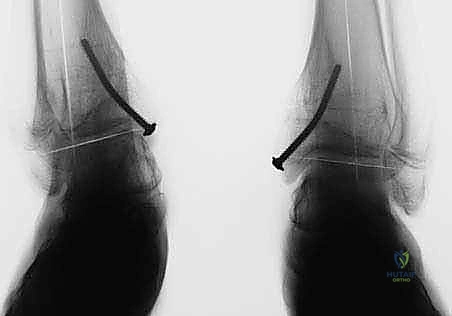

كيف تعمل التقنية؟

يشبه الأمر تماماً تقويم الأسنان. يقوم الأستاذ الدكتور محمد هطيف بتركيب شريحة معدنية صغيرة جداً (تُعرف بشريحة الـ 8-Plate أو شريحة الشد) على الجانب الداخلي (الأسرع نمواً) من مركز النمو في أسفل عظمة الساق. هذه الشريحة تعمل كمكبح لطيف؛ فهي تبطئ النمو في الجانب الداخلي، بينما تسمح للجانب الخارجي بالاستمرار في النمو بشكل طبيعي. بمرور الأشهر، وبفضل استمرار نمو الطفل، "يُعدّل" الكاحل نفسه تدريجياً ويستقيم محوره تماماً.

الخطوة الرابعة: تثبيت الشريحة (8-Plate)

بمهارة فائقة، يقوم الدكتور هطيف بوضع الشريحة المعدنية المصنوعة من التيتانيوم الطبي النقي فوق مركز النمو. يتم تثبيت الشريحة باستخدام مسمارين صغيرين؛ أحدهما فوق خط النمو والآخر تحته. هذه المسامير لا تخترق مركز النمو نفسه، مما يضمن عدم تدميره.